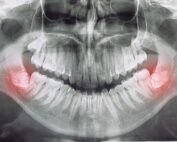

Ortodoncia en niños, ¿a partir de qué edad es aconsejable comenzar la revisiones?